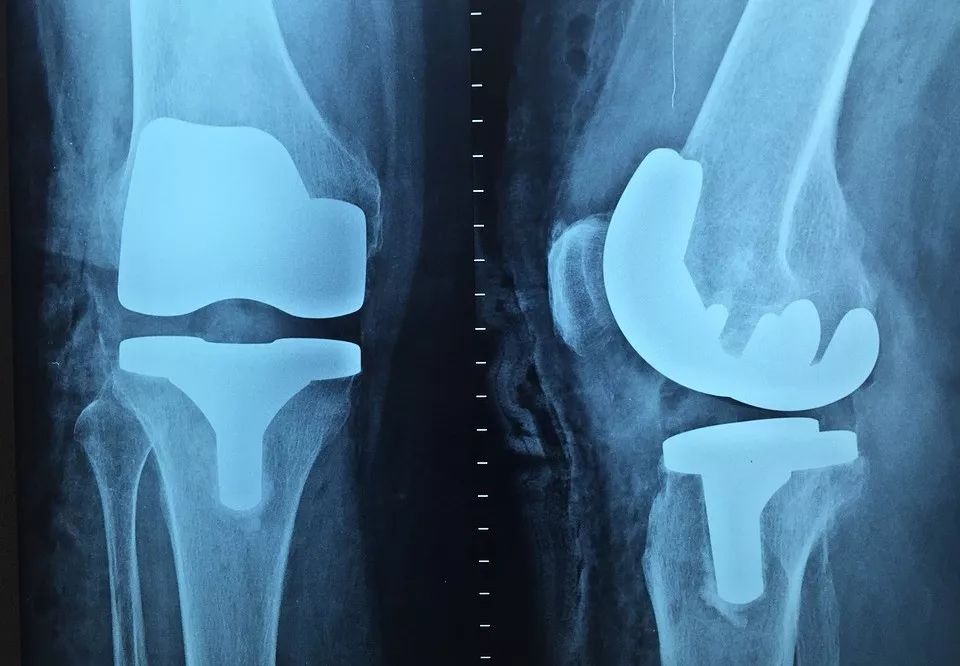

轻微骨刺可以通过适度的按摩、运动、热敷、服用镇痛药来缓解,严重时需 手术切除,但复发率较高。长期活动受限者可考虑置换关节。

【检查方式】 X线平片可以检出较为明显的骨刺,以及病变的程度和范围;CT检查更能发现轻微病变;如果伴随有高热、多关节疼痛,还需增加检查血常规、血沉、C反应蛋白等指标。

【检查方式】一是从动作来判断:双脚并拢站立,膝盖处缝隙越大说明骨骼错位越严重;上楼梯时会有明显的疼痛、乏力感,脚底像踩着棉花。二是进行影像学检查。